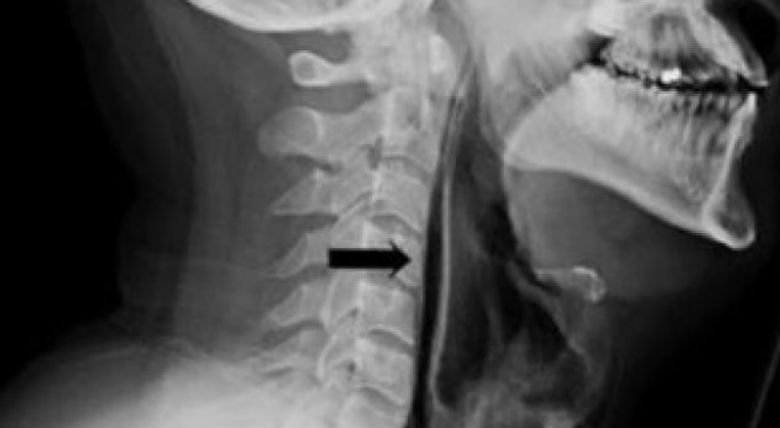

E mbani teshtimën? Ja nga çfarë rrezikoheni?

Nëse jeni gati duke teshtitur, edhe nëse jeni në një vend të qetë, mjekët rekomandojnë që ta nxirrni teshtimën. Një 34-vjeçar nga Britania, emri i të cilit nuk bëhet i ditur, e mori këtë...